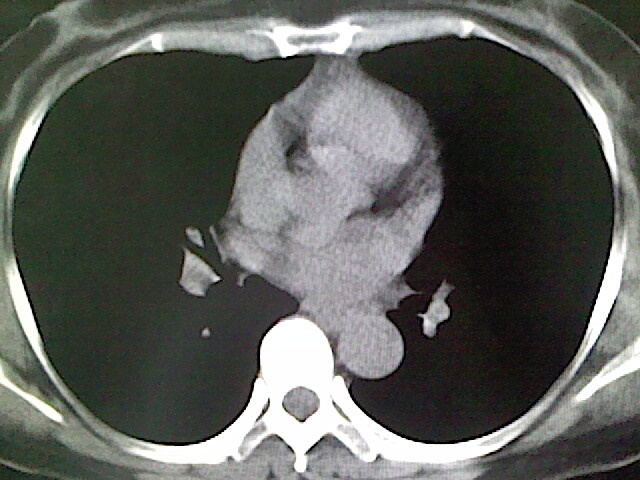

女,52岁,咳嗽,咳痰多日

左下肺陈旧纤维索条!

左肺舌段炎性改变

我见过几例,为炎症后纤维条索

慢性炎症后改变

考虑慢性炎性病灶粘连牵拉改变。

左肺舌叶纤维锁条病变。

左肺上叶下舌段炎症并局部胸膜反应。

左肺舌叶纤维索条影。

左肺舌叶段陈旧性病变

左肺舌段炎性反应。片子的质量太不好了。

左肺舌段炎性

炎性改变

左肺舌叶纤维索条影